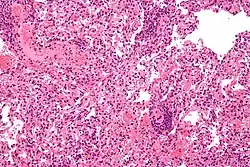

![]() صورة مجهرية تظهر رفض زرع الرئة صورة مجهرية تظهر رفض زرع الرئة | |

إن تشخيص الرفض الحاد يعتمد على البيانات المسجلة سريريا، بما في ذلك علامات وأعراض المريض والفحوصات المخبرية وبصورة أساسية الخزعة المأخوذة من النسيج. يقوم أخصائي علم الأمراض بتحليل الخزعة وبدوره سيلاحظ التغيرات في الأنسجة والتي تشير إلى وجود الرفض. وبصورة عامة فإن أخصائي علم الأمراض يقوم بالبحث عن المميزات النسيجية والرئيسية الثلاثة. أولا، وجود خلايا T التي تتسرب إلى الأنسجة المزروعة؛ وهذا التسرب يمكن أن يرافقه وجود مجموعة غير متجانسة من أنواع الخلايا الأخرى بما في ذلك الحمضيات، وخلايا البلازما والعدلات. (إن نسبة هذه الأنواع من الخلايا قد تكون مفيدة في تشخيص نوع الرفض.) ثانيا، الدلالة بإصابة هيكلية للأنسجة المزروعة؛ تعتمد سمات هذه الإصابة على نوع الأنسجة التي تم زرعها. وأخيرا، إصابة الأوعية الدموية في الأنسجة المزروعة.